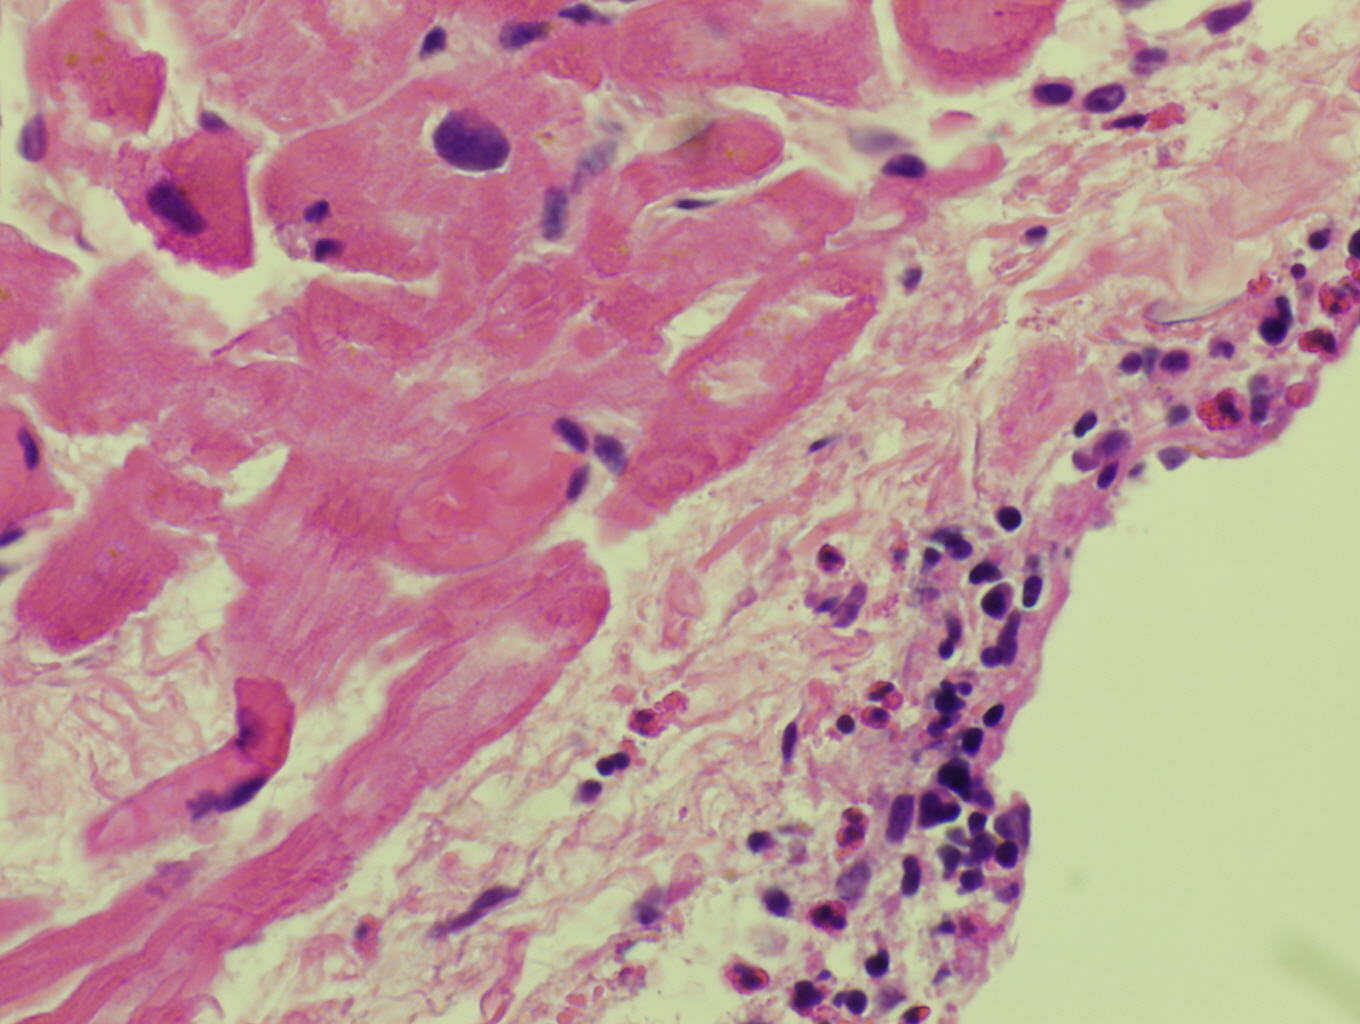

Hematoxylin and Eosin stained endomyocardial biopsy showing eosinophilic infiltration of endocardium in eosinophilic myocarditis

Histopathologic features are dependent on the organs involved. Eosinophilic infiltration is noted on diagnostic tissue biopsy. Eosinophilia and increased eosinophilic precursors can be identified on trephine bone marrow biopsy and peripheral blood smears. There is no histologic correlate to clonality, and genetic studies are required for diagnosis.